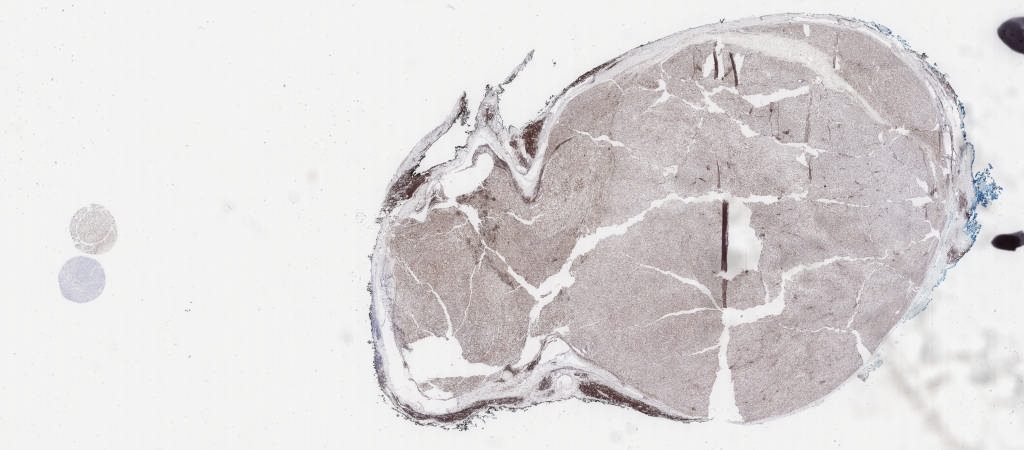

ini.svs

139440

x

61556

@

40X